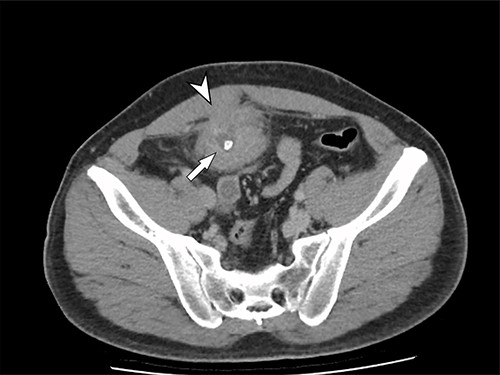

A 41-year-old, previously well, male presented to the emergency department with lower abdominal pain, pyrexia with a temperature of 38.2°C and a palpable suprapubic mass. His relevant background history included an uneventful laparoscopic appendicectomy 2 years prior for acute appendicitis, insulin independent type 2 diabetes and hypertension. He presented with raised inflammatory markers and computed tomography (CT) showing a well circumscribed central pelvis lesion that appeared concerning for a urachal malignancy (Fig. 1). This lesion was closely associated with the dome of the bladder (Fig. 2). This supracystic lesion measured 58 mm × 56 mm with central cystic component of 15 mm in diameter, and contained a 11 mm central calcification. Further characterization with magnetic resonance imaging showed possible extension of this mass to the rectus abdominis without significant lymphadenopathy (Fig. 3). Flexible cystoscopy only found inflammation at the dome. As urachal malignancy could not be unequivocally excluded on imaging studies alone, following multidisciplinary discussion, the decision was made to perform an excision of this lesion.

Axial MRI image of lesion. Arrowhead indicated involvement with the rectus abdominis. Arrow indicates lesion and calcific focus.